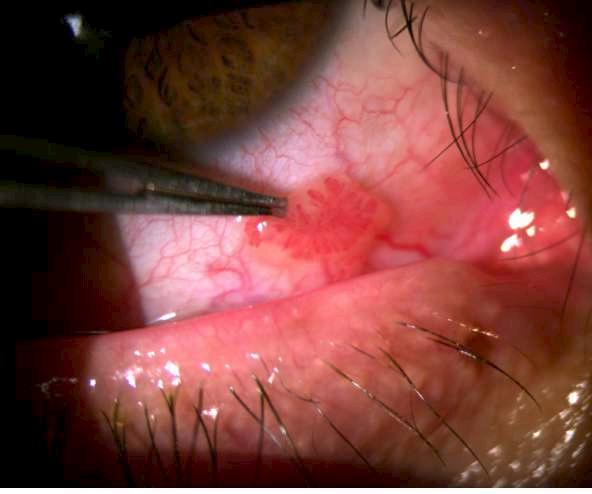

1.A. GRANULOMA PIÓGENO

Imagen aportada por Dr. Álvaro Rodriguez

Bü Lesión pedunculada y aspecto papilomatoso de color sonrosado que se desarrolla después de un trauma quirúrgico, accidental o un proceso inflamatorio local (chalazión o reacción a cuerpo extraño)

ü EL diagnóstico diferencial debe realizarse principalmente con un papiloma pediculado, con el que generalmente le diferencia la velocidad de progresión y el antecedente de traumatismo o chalazión.

Arch Soc Esp Oftalmol vol.84 No.1 ene.2009

Saornil MA, Becerra E, Mendez MC, Blanco G. Tumores de la conjuntiva. ü

A

Imagen A y B muestran un granuloma a nivel del canto medio del ojo derecho.